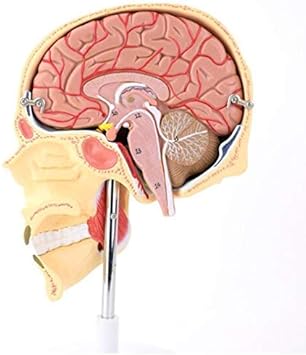

Decorso del nervo ottico e rapporto con altre strutture anatomiche Principali malattie del nervo ottico Il nervo ottico rappresenta l'inizio delle vie ottiche, ossia quell'insieme di strutture che, partendo dalla retina, collegano il bulbo oculare al cervello Questa componente è indispensabile per attivare in modo corretto la visione. Decorso del nervo ottico e rapporto con altre strutture anatomiche Principali malattie del nervo ottico Il nervo ottico rappresenta l'inizio delle vie ottiche, ossia quell'insieme di strutture che, partendo dalla retina, collegano il bulbo oculare al cervello Questa componente è indispensabile per attivare in modo corretto la visione. Poiché i pazienti possono danneggiare un solo nervo olfattivo alla volta, che non possono essere immediatamente a conoscenza del danno, attribuendo una diminuzione del senso dell'olfatto per il naso chiuso o non se ne accorga la sensibilità ridotta agli odori.

Il nervo olfattivo è la coppia di nervi cranici con funzione sensitiva deputata alla trasmissione dell'informazione olfattiva all'encefalo;. Anatomia Il nervo ottico è il secondo di 12 paia di nervi cranici, ma è considerato come parte del sistema nervoso centrale;. Infatti, le fibre sono ricoperte dalla mielina prodotta dagli oligodendrociti, e il nervo ottico è avvolto nelle meningi (dura madre, aracnoide, pia madre) Tecnicamente, assieme al nervo olfattivo, non sono nervi ma una continuazione del sistema nervoso centrale.

Il nervo ottico è uno dei dodici nervi cranici Si può definire una proiezione esterna del sistema nervoso centrale grazie a cui gli impulsi luminosi percepiti dalla retina vengono veicolati verso la corteccia occipitale dove vengono convertiti in sensazione visiva E’ composto da oltre un milione di fibre che si raccolgono in fasci separati da. I nervi infiammati sono, spesso, una patologia di facile risoluzione In altri casi, invece, possono essere un campanello d’allarme per problemi più seri, carenze vitaminiche, soprattutto di B12 o patologie di base correlate I nervi infiammati si definiscono, in medicina, “neuropatia”, in quanto possono dipendere sia da una causa neurologica che da una causa nervosa Indice1. Controlla anche la dimensione delle pupille in risposta alla luce.

Il nervo glossofaringeo (in lingua inglese glossopharyngeal nerve) è il nono nervo appartenente al gruppo dei nervi cranici (IX nervo cranico) E' un nervo pari e simmetrico, cioè esiste un nervo glossofaringeo di destra ed uno di sinistra Funzioni Il IX nervo è un nervo misto è motore per il muscolo stilofaringeo e per il costrittore superiore della faringe;. Senso dell’olfatto danneggiato o alterato – Staminali coltivate in provetta per ripararlo “Possono rigenerare i tessuti danneggiati del naso Coltivate per la prima volta in provetta delle cellule staminali capaci di rigenerare l’epitelio olfattivo del naso l’esperimento, condotto per ora con cellule di topo, è un’importante prova di principio che apre alla possibilità di. Il nervo ottico è uno dei dodici nervi cranici Si può definire una proiezione esterna del sistema nervoso centrale grazie a cui gli impulsi luminosi percepiti dalla retina vengono veicolati verso la corteccia occipitale dove vengono convertiti in sensazione visiva E’ composto da oltre un milione di fibre che si raccolgono in fasci separati da.